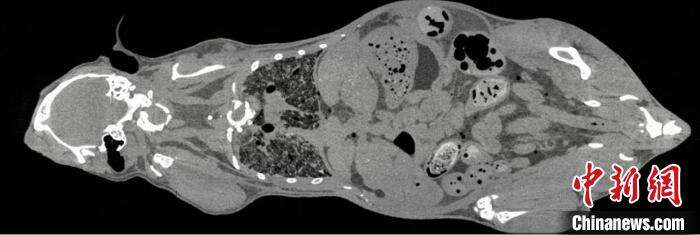

鼠全身成像。 中科院高能所 供图